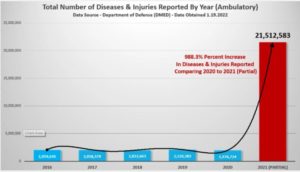

DOD Caught in MAJOR SCANDAL: US Military Caught in Severe Data Manipulation Following COVID Reveal — No Way “Revised” Numbers Are Real

A recent report by Daniel Horowitz at The Blaze on the Department of Defense manipulating epidemiological data after the initial data for 2021 revealed a MASSIVE increase, by 988%, in doctor visits by US military members in 2021.

What happened in 2021? Could it be the mandatory COVID vaccines?

The initial data was presented during Sen.… Read the rest